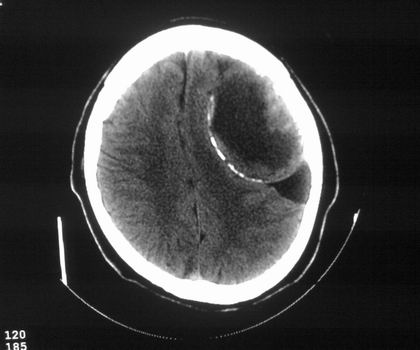

以下是引用影像孺子牛在2008-4-29 21:20:00的发言:[br]首先病变定位在脑外,根据ct密度及mri信号特征考虑慢性硬膜下血肿不连续环形钙化。

以下是引用周战梅在2008-4-29 23:12:00的发言:[br]脑外病变,蛛网膜下腔增宽,囊壁点状、环形钙化,增强扫描呈不均匀环状强化,考虑为囊性脑膜瘤可能性大,慢性脓肿、血肿机化、胆脂瘤不能除外。